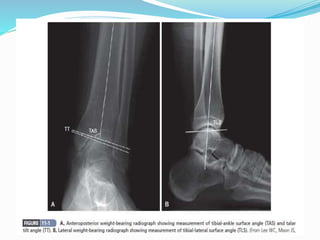

 For determination of involvement of compartment of

tibial articular surface for supramalleolar corrective

osteotomy.

 TIBIO- TALAR AXIS

 TIBIAL LATERAL SURFACE ANGLE.